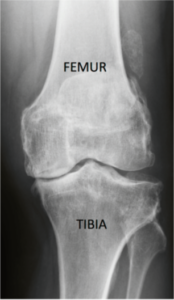

Das Kniegelenk funktioniert ähnlich wie ein Scharniergelenk, bestehend aus dem Oberschenkelknochen (Femur), dem Schienbein (Tibia) und der Kniescheibe (Patella), die jeweils mit Knorpel auf der Gelenkfläche überzogen sind. Das Wadenbein (Fibula) ist nicht direkt an den Gelenkflächen beteiligt, ist jedoch Ansatzpunkt des äußeren Seitenbandes (Abb. 1). Wir unterscheiden 3 Gelenkanteile, wo sich eine Arthrose ausbilden kann. Im Mittelpunkt steht hierbei die Verbindung zwischen Schienbein und Oberschenkel (=Tibiafemoralgelenk) bzw. zwischen dem Oberschenkelknochen und der Rückfläche der Kniescheibe (=Femoropatellargelenk).